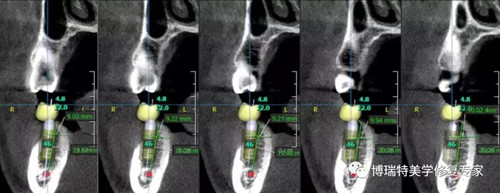

自1971年第一张人脑CT图诞生至今,技术革命在不断快速迭代。智能3D全景可以帮助医生便捷直观地发现多种牙齿隐患问题,医患沟通变得简单且高效。OnDemand 3D后处理软件直接模拟真实种植场景,使得医患沟通更直观,手术更安全,患者更信任。

骨密度精确测量